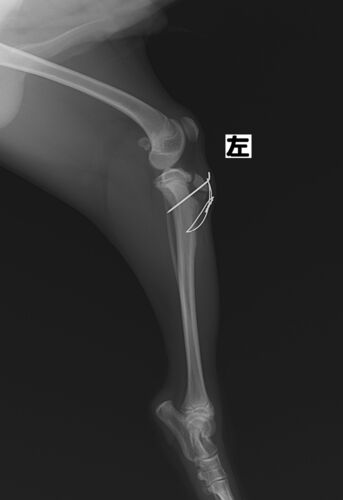

脛骨粗面剥離骨折の犬の1例

今回の症例は生後約6ヶ月のワンちゃん。 左後肢の脛骨粗面の剥離骨折で来院されました。 レントゲン検査にて、右の後肢と比べると、左後肢の脛骨粗面の近位の変位が確認できます。 正常な右後肢 脛骨粗面が骨折した左後肢 この部位の骨折は、生後10ヶ月以下…